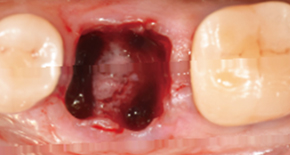

1. Extraction